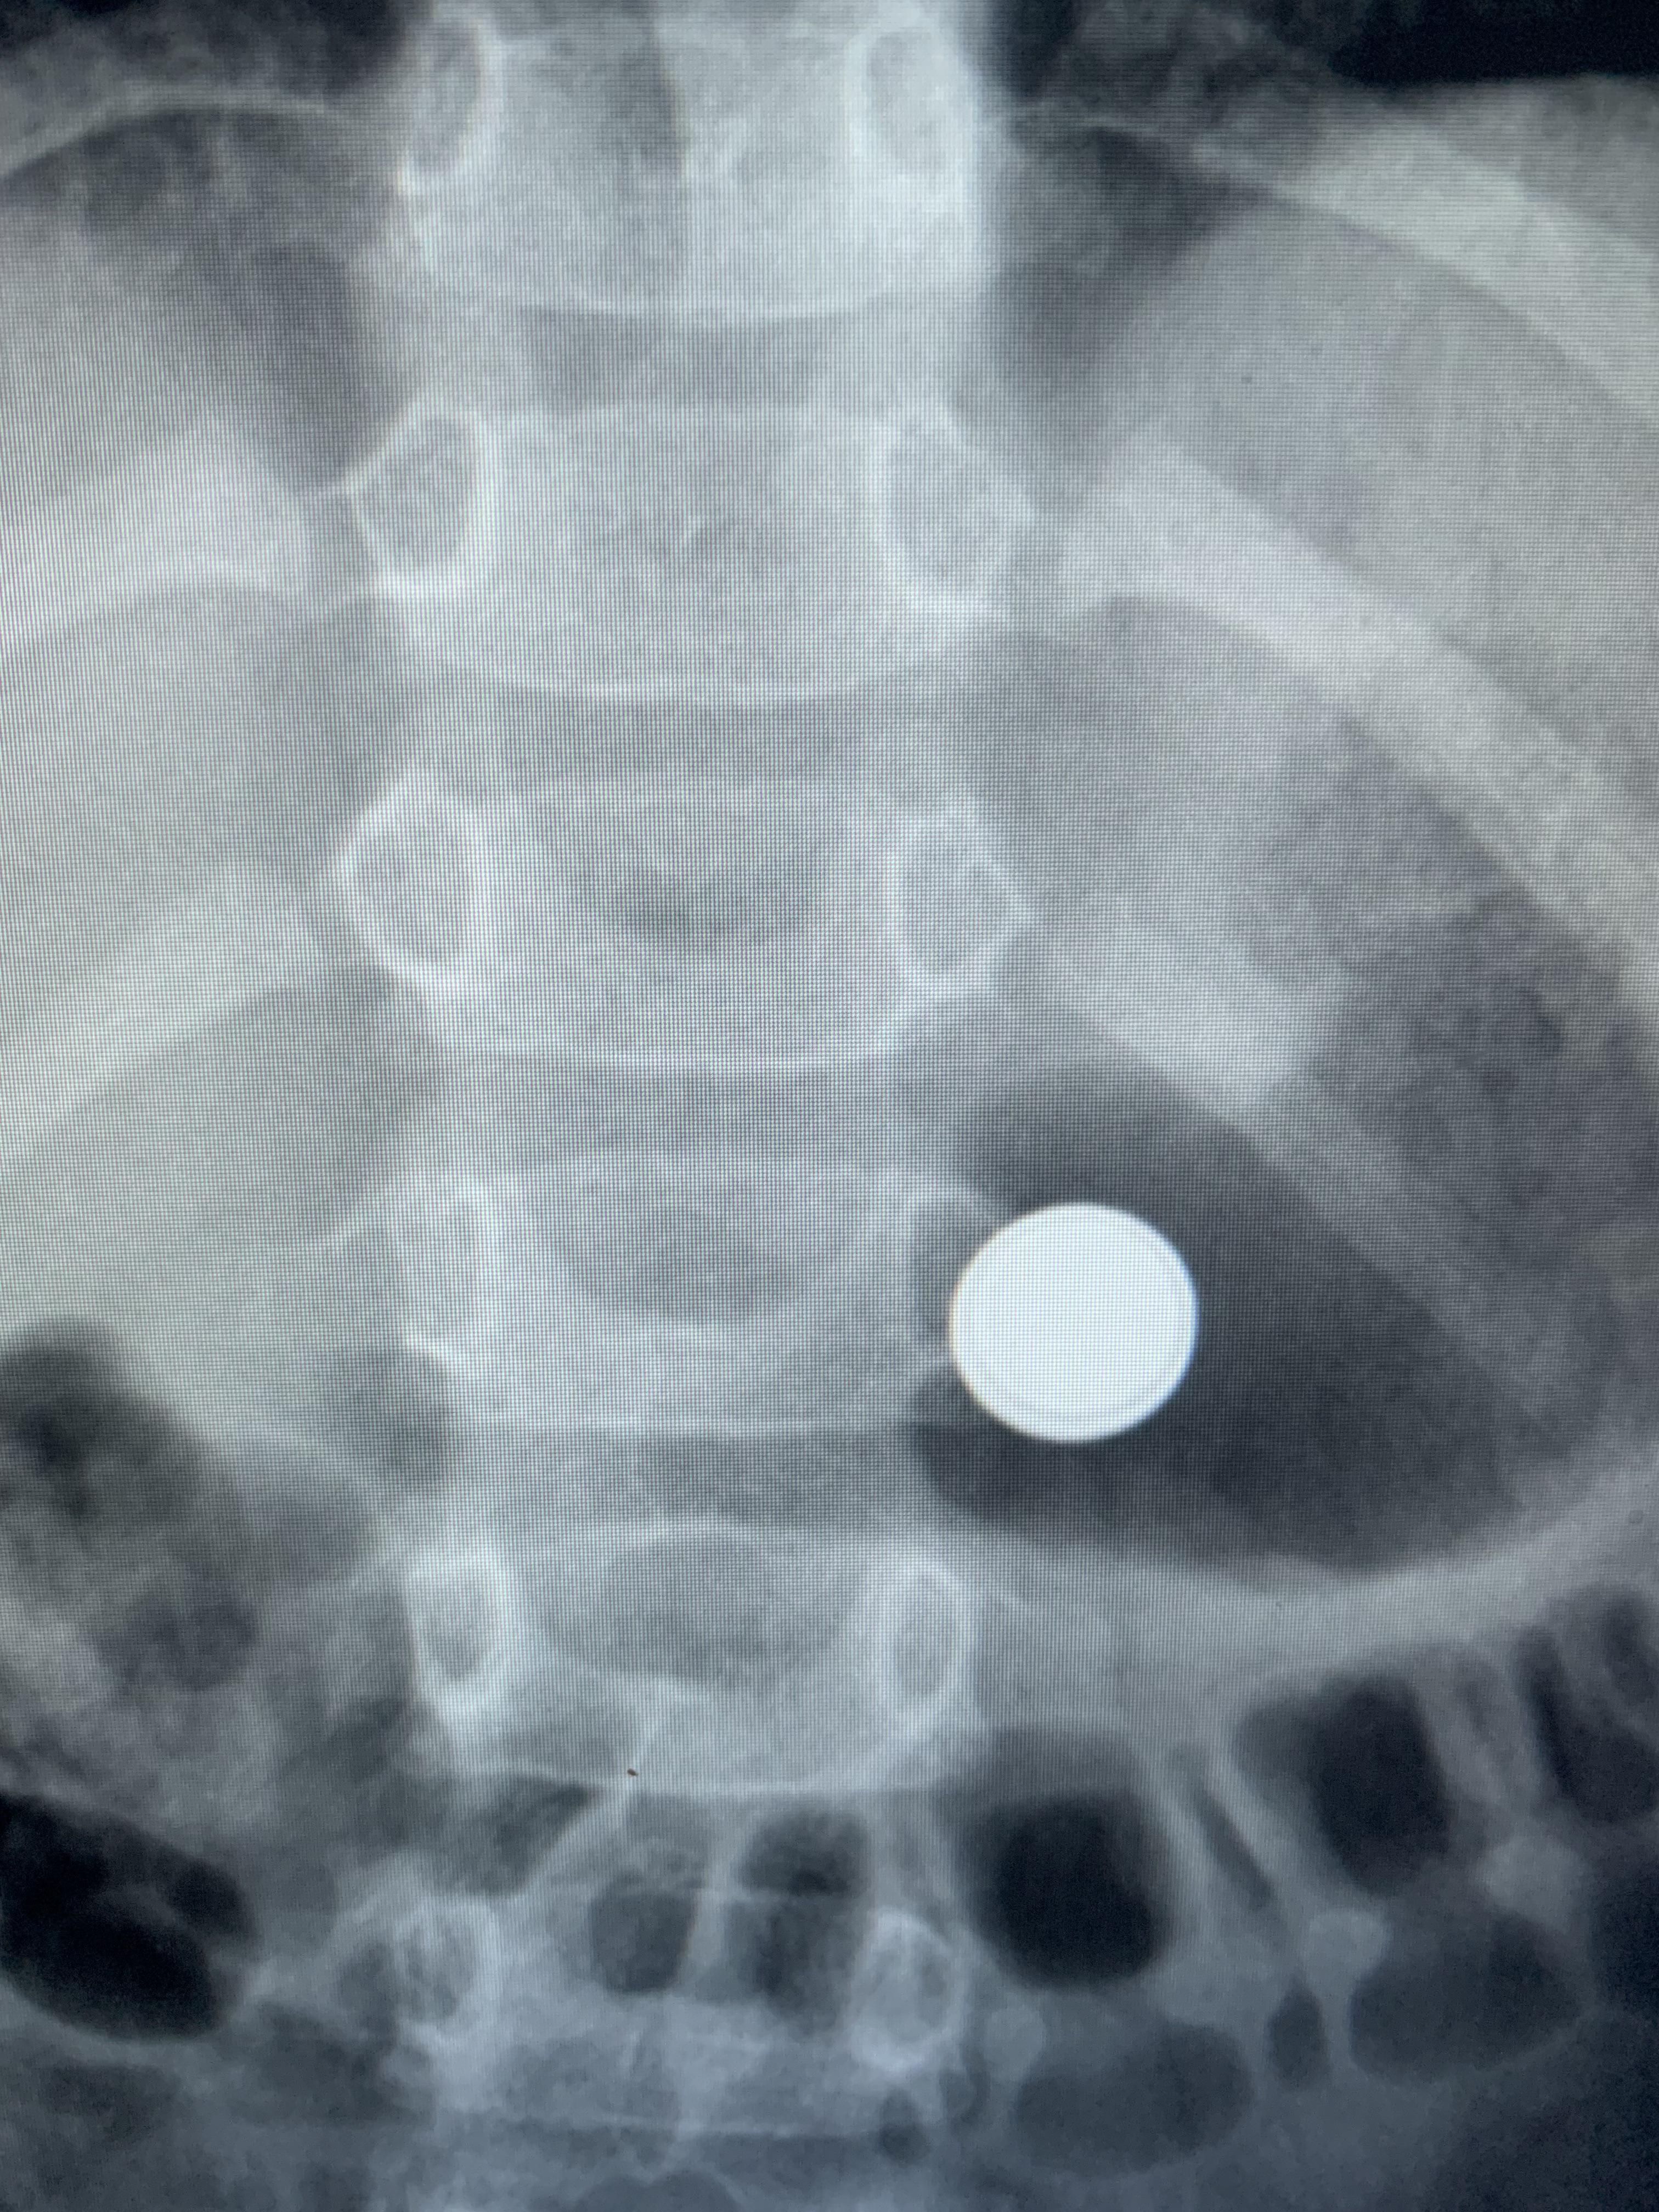

Coin vs battery Image Coin Vs Battery Radiology Hydroxide radicals produced by the button battery lodged in the esophagus can cause caustic injury, necrosis, perforation, fistula and strictures in the esophagus. Ingestion of foreign body is a common problem in children and it is important to differentiate between button battery and coin ingestion. This is because of the difference in terms of. Importantly, a “halo” sign distinguishes a. Coin Vs Battery Radiology.

Coin vs battery Image Coin Vs Battery Radiology Importantly, a “halo” sign distinguishes a battery from another foreign body like a coin (figure 1) and it is vital that healthcare professionals recog. Hydroxide radicals produced by the button battery lodged in the esophagus can cause caustic injury, necrosis, perforation, fistula and strictures in the esophagus. This is because of the difference in terms of. Ingestion of foreign body. Coin Vs Battery Radiology.

Coin ingestion Radiology Cases Coin Vs Battery Radiology Hydroxide radicals produced by the button battery lodged in the esophagus can cause caustic injury, necrosis, perforation, fistula and strictures in the esophagus. Importantly, a “halo” sign distinguishes a battery from another foreign body like a coin (figure 1) and it is vital that healthcare professionals recog. This is because of the difference in terms of. Ingestion of foreign body. Coin Vs Battery Radiology.

Coin ingestion Radiology Cases Coin Vs Battery Radiology Hydroxide radicals produced by the button battery lodged in the esophagus can cause caustic injury, necrosis, perforation, fistula and strictures in the esophagus. Ingestion of foreign body is a common problem in children and it is important to differentiate between button battery and coin ingestion. Importantly, a “halo” sign distinguishes a battery from another foreign body like a coin (figure. Coin Vs Battery Radiology.

Xray showing a coin lithium battery (CR 2025) located in the fundus of Coin Vs Battery Radiology Ingestion of foreign body is a common problem in children and it is important to differentiate between button battery and coin ingestion. This is because of the difference in terms of. Importantly, a “halo” sign distinguishes a battery from another foreign body like a coin (figure 1) and it is vital that healthcare professionals recog. Hydroxide radicals produced by the. Coin Vs Battery Radiology.